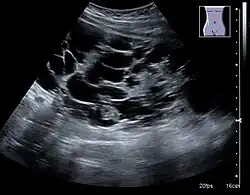

The hydronephrosis is typically graded visually and can be divided into five categories going from a slight expansion of the renal pelvis to end-stage hydronephrosis with cortical thinning (Figure 15). The evaluation of hydronephrosis can also include measures of calyces at the level of the neck in the longitudinal scan plane, of the dilated renal pelvis in the transverse scan plane and the cortical thickness, as explained previously (Figure 16 and Figure 17).[1]

Figure 15. End-stage hydronephrosis with cortical thinning. Measurement of pelvic dilatation on the US image is illustrated by '+' and a dashed line.[1] -

Figure 16. Hydronephrosis with dilated anechoic pelvis and calyces, along with cortical atrophy. The width of a calyx is measured on the US image in the longitudinal scan plane, and illustrated by '+' and a dashed line.[1] -